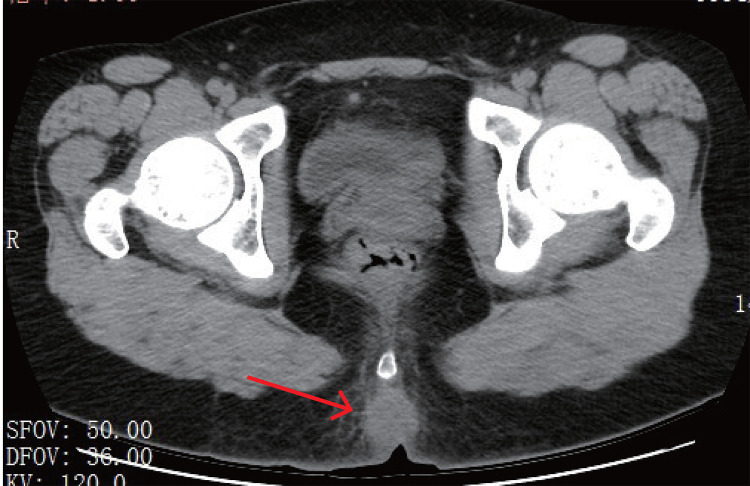

Sacrococcygeal pilonidal abscesses are typically caused by anaerobic and Gram-negative bacteria due to their anatomical proximity to the anus; however, mixed infections involving Actinomyces and Actinotignum species are exceptionally rare, and to our knowledge, this is the first reported case of a sacrococcygeal pilonidal abscesses caused by Actinomyces turicensis and Actinotignum schaalii. The patient, an 18-year-old female, presented with one week of localized pain, redness, and swelling, which failed to respond to conventional antibiotics. Pelvic CT revealed an abscess, prompting surgical debridement and subsequent recovery. Rapid pathogen identification was achieved using Matrix-Assisted Laser Desorption/Ionization Time-of-Flight Mass Spectrometry (MALDI-TOF MS) from a single colony culture. This case underscores the importance of microbiological identification using tools like MALDI-TOF MS to recognize uncommon pathogens, which is critical for avoiding ineffective empiric antibiotics and guiding appropriate therapy. Further research is needed to optimize management strategies for such rare infections.